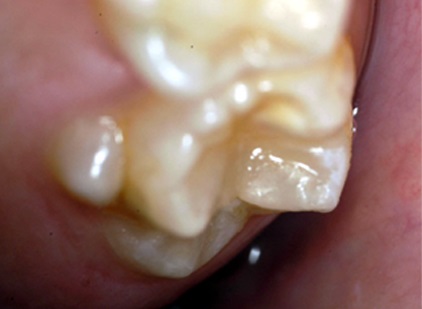

Abrasion sur molaires touchées par une amélogénèse imparfaite (universitederennes1)

Abrasion sur molaires touchées par une amélogénèse imparfaite (Université de Rennes1)